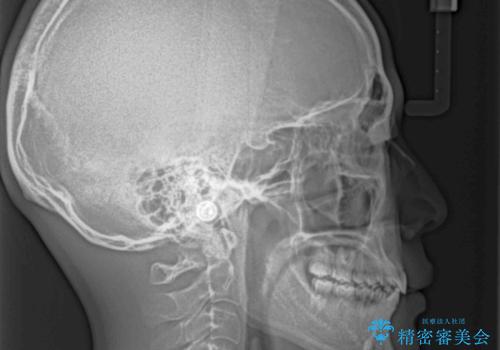

- 上下前歯のデコボコと深い咬み合わせを気にして来院された患者様です。

下顎前歯が一本欠損しており、下顎の歯列が小さいため、ディープバイトになりやすい状態でした。

傾斜しいている大臼歯を立ち上げながら、下顎歯列を上顎に対して前方位となるように工夫し、デコボコを解消した上でディープバイトも改善することができました。